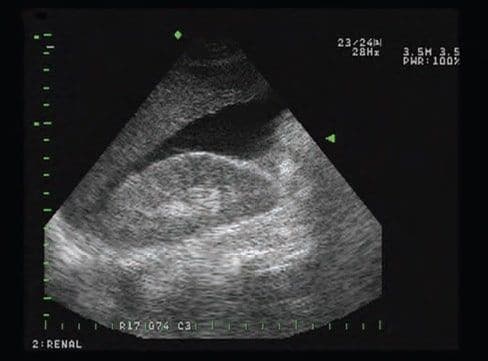

За належного виконання досвідченою особою FAST є прийнятним, швидким і надійним дослідженням для виявлення рідини в черевній порожнині (зобр. 5–4). Як спосіб оцінки, що може бути повторений у динаміці потрібну кількість разів, FAST дозволяє також виключити тампонаду серця як одну з негіповолемічних причин гіпотензії.

Зобр. 5–4. Сфокусована оцінка за допомогою сонографії на предмет травми (FAST). У FAST для виявлення наявності гемоперитонеуму використовується ультразвукова технологія.

FAST включає дослідження чотирьох ділянок: перикарду, простору між печінкою та правою ниркою, селезінково-ниркового простору та простору Дугласа (зобр. 5–5. A).

Зобр. 5–5. A. Розташування зондів.

Після проведення первинного дослідження медичний працівник може виконати одне або кілька повторних, щоб виявити прогресуючий гемоперитонеум (зобр. 5–5. B).

Зобр. 5–5. B. FAST-зображення правого верхнього квадранту, що показує печінку, нирки та вільну рідину.

FAST можна проводити біля ліжка у місці надання допомоги одночасно з іншими діагностичними або терапевтичними процедурами. Див. додаток G «Навички циркуляції» та FAST відео.